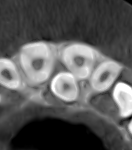

Los dientes incluidos, como caninos o muelas del juicio, son una situación frecuente en odontología. Aunque la ortopantomografía suele ser la primera prueba diagnóstica, en muchos casos no ofrece información suficiente para planificar el tratamiento con seguridad, especialmente cuando existen dudas sobre la posición real del diente o su relación con estructuras cercanas.

Al tratarse de una imagen bidimensional, la panorámica puede presentar superposiciones y distorsiones que dificultan la interpretación. En estos casos, el CBCT (Tomografía de Haz Cónico) permite un estudio tridimensional preciso, aportando la información necesaria para una correcta toma de decisiones clínicas.

El CBCT proporciona una visión 3D completa que permite:

- Localizar el diente incluido con precisión.

- Evaluar su angulación y cercanía a otras piezas dentarias.

- Detectar posibles reabsorciones radiculares.

- Planificar extracciones o tracciones ortodóncicas con mayor seguridad.

Esta información es especialmente relevante en caninos incluidos, donde una planificación adecuada reduce riesgos y mejora el pronóstico del tratamiento.